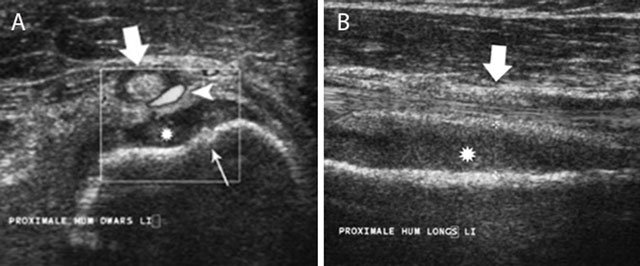

Figure 6

Acute childhood osteomyelitis of the proximal humerus on ultrasound. Transverse (a) and longitudinal (b) ultrasound images of the proximal humerus. Note focal thinning of the humeral cortex (thin white arrow) on the axial images in keeping with a cortical penetration of the infection causing subperiosteal pus collection (asterisk). There is also increased Doppler signal (white arrow head) within the synovium of the long head of the biceps tendon (large white arrow).